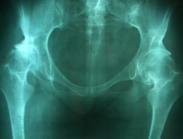

股骨頭壞死

股骨頭壞死(osteonecrosis of the femoral head ,ONFH)又稱股骨頭缺血性壞死(avascularnecrosis ,AVN),是骨科領域常見的難治性疾病。ONFH可分為創傷性和非創傷性兩大類,前者主要是由股骨頸骨折、髖關節脫位等髖部外傷引起,后者在我國的主要原因為皮質類固醇的應用及酗酒。中醫認為疾病發生原因為外因和內因,且內因外因相互作用,使人體陰陽失去平衡,氣血的失恒而生疾,亦稱"髀樞痹"、"骨痹"、"骨萎"。 股骨頭壞死是一個病理演變過程,初始發生在股骨頭的負重區,先破壞鄰近關節面組織的血液供應,進而造成壞死。其主要癥狀,從間斷性疼痛逐漸發展到持續性疼痛,再由疼痛引發肌肉痙攣、關節活動受到限制。修復不完善,損傷-修復的過程繼續,導致股骨頭結構改變、股骨頭塌陷、變形,關節炎癥,功能障礙,最后造成嚴重致殘而跛行。股骨頭壞死固然會引起病痛,關節活動和負重行走功能障礙,但不要受“壞和死”文字含義恐怖的影響,股骨頭壞死病變,畢竟局限,累及個別關節,可以減輕,消退和自愈,即便嚴重,最后還可以通過人工髖關節置換補救,仍能恢復步行能力。股骨頭缺血性壞死理想的治療應在早期階段,尤其在X線發現之前,如果迅速采取有效措施,可防止股骨頭塌陷,保護關節功能。